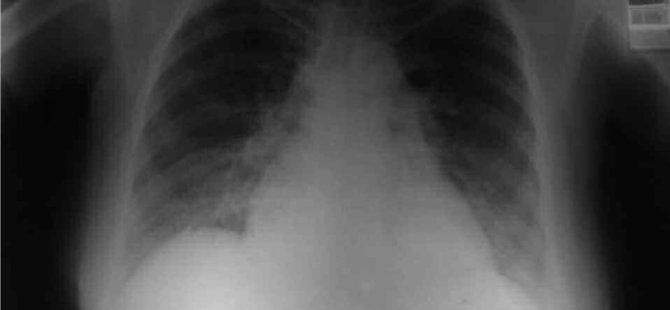

Sağlık Bakanı Fahrettin Koca, 25 Temmuz günü koronavirüs verilerini açıklarken, Kocaeli’ni pnömonili hasta sayısı oranı en çok artan iller arasında saymıştı. Zatüre anlamına gelen pnömonili vakalarındaki artış endişelendirmişi. Bakan Koca’nın bu açıklamasının ardında ise bir skandal ortaya çıktı. Kocaeli’de verilerin eksik girildiği ortaya çıktı. Sağlık Müdürlüğü’nün pnömonili verilerini yanlış girmesi sonrası ise Bakan Kocae böyle bir açıklama yapmak zorunda kalmıştı. İl Sağlık Müdürü Şenol Ergüney ise şunu doktorlara atarak, “1 hafta önce bazı doktorlarımız pnömonil verilerini eksik girmiş. Bunu fark ettik ve düzelttik. Düzeltince de doğal olarak verilerimiz yüksek gözüktü” dedi.Bu skandal olay sonrası ise Kocaeli ile ilgili bilgilerin ne kadar doğru olduğu ise tartışma konusu oldu.

Kocaeli’nin “Pnömonili” verilerini yanlış girmişler!

Sağlık Bakanı Fahrettin Koca’nın geçtiğimiz gün açıkladığı verilerde Kocaeli’nin “Pnömonili” verisi en yüksek çıkan iller arasında sayması sonrası, Sağlık Müdürlüğü’nün verileri yanlış girdiği ortaya çıktı